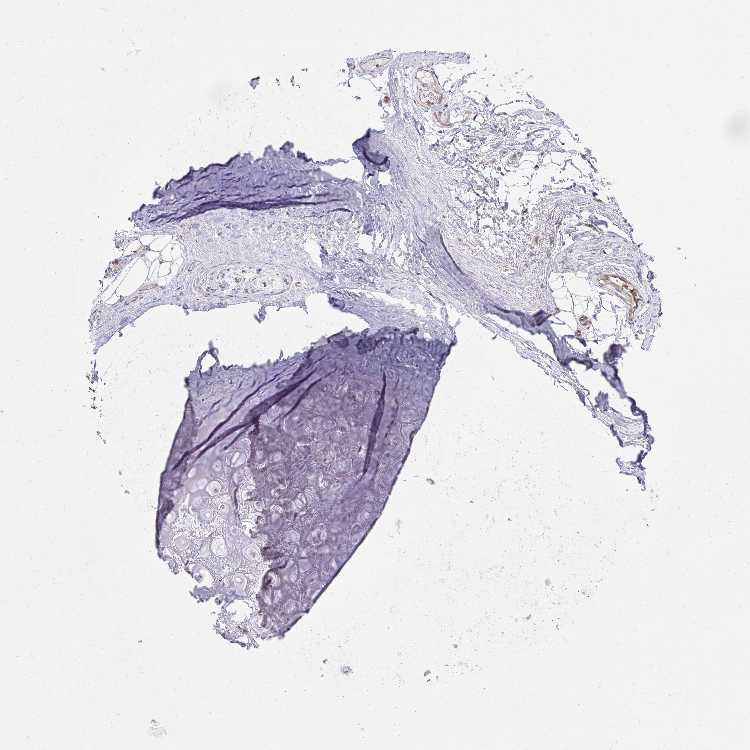

ADIPOSE TISSUE - Antibody stainingi

Antibody staining in the annotated cell types in the current human tissue is reported as not detected, low, medium, or high, based on conventional immunohistochemistry profiling in selected tissues. This score is based on the combination of the staining intensity and fraction of stained cells.

Each image is clickable and will lead to virtual microscopy that enables deeper exploration of all samples and also displays staining intensity scores, fraction scores and subcellular localization as well as patient and tissue information for each sample.

Antibody HPA011136Antibody HPA048565Antibody CAB037292Antibody CAB080440

Adipocytes Not detectedNot detectedMediumNot detected